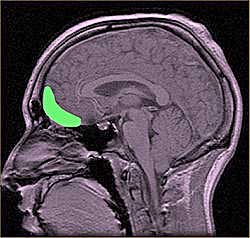

El estudio, dirigido por Anderson y cols. (2014) de la Universidad de Iowa y publicado en el Journal of Neuroscience, encontró que los niveles elevados de cortisol fueron asociados con una pérdida de la sinapsis en el prefrontal, una estructura importante para el funcionamiento de la memoria a corto plazo.

Al momento de examinar los cerebros, se encontró que las ratas más estresadas y olvidadizas tenían un 20% menos de sinapsis en el cortex prefrontal, sugiriendo esto que la causa de pérdida de memoria a corto plazo es debida al estrés sufrido.

Los investigadores descubrieron que las personas afectadas presentaban una reducción significativa en la materia gris, una zona del hipocampo relacionada con la memoria que daba como resultado una pérdida de memoria.

Los resultados demostraron que la presencia de demasiado cortisol en el cerebro produce una reducción de la materia gris del hipocampo, lo que explica la pérdida irreversible de memoria. Se sugiere también una evaluación para comprobar el daño que puede causar el estrés cotidiano, así como el empleo que hacen algunas personas de fármacos glucorticoides, como la cortisona, que son antiinflamatorios y que imitan la acción del cortisol.